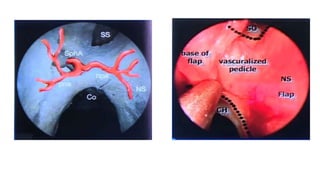

This document discusses the microanatomy of the sellar and suprasellar regions as well as operative approaches for accessing these areas. It describes the bones, venous connections, arterial relationships and incisura spaces in the regions. Several surgical approaches are mentioned, including sublabial, transseptal, endonasal, and subfrontal transfrontal transsphenoidal approaches. Key anatomical structures like the optic chiasm, carotid protuberance, cavernous sinus and clival indentation are located using an "owl eye" panoramic view of the fetal face mimicking centers.